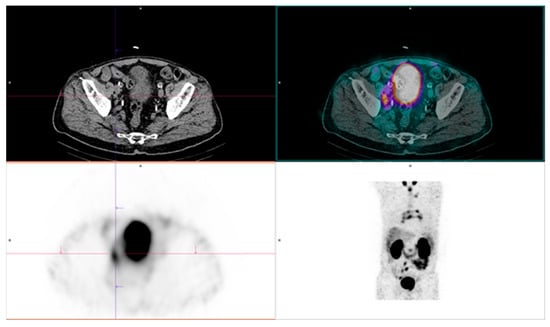

Article

Background: While gallium-68 has traditionally dominated PET imaging in oncology, copper radionuclides have sparked interest for their potential applications in nuclear medicine and theranostics. Considering the advantageous physical decay properties of copper-61 compared to those of gallium-68, we describe a fully automated GMP-compliant synthesis process for 61Cu-based radiopharmaceuticals and demonstrate their in vivo application for targeting the overexpressed PSMA by PET/MR imaging. Methods: Copper-61 was obtained through the irradiation of natural zinc liquid targets in a biomedical cyclotron. [61Cu]Cu-DOTAGA-PSMA-I&T and [61Cu]Cu-NODAGA-PSMA-I&T were produced without manual intervention in two Synthera® Extension modules. Radiochemical purity was analyzed by radio-HPLC and iTLC. Cellular uptake was evaluated in LNCaP and DU145 cells. In vivo PET/MRI was performed in control mice to evaluate the biodistribution of both radiopharmaceuticals, and in tumor-bearing mice to assess the targeting ability towards PSMA. Results: The fully automated process developed proved to be effective for the synthesis of 61Cu-based radiopharmaceuticals, with appropriate molar activities. The final products exhibited high radiochemical purity (>98%) and remained stable for up to 6 h after the EOS. A time-dependent increase in cellular uptake was observed in LNCaP cells, but not in DU145 cells. As opposed to [61Cu]Cu-NODAGA-PSMA-I&T, [61Cu]Cu-DOTAGA-PSMA-I&T exhibited poor kinetic stability in vivo. Subsequent PET/MR imaging with [61Cu]Cu-NODAGA-PSMA-I&T showed tumor uptake lasting up to 4 h post-injection, predominant renal clearance, and no detectable accumulation in non-targeted organs. Conclusions: These results demonstrate the feasibility of the implemented process, which yields adequate amounts of high-quality radiopharmaceuticals and can be adapted to any standard production facility. This streamlined approach enhances reproducibility and scalability, bringing copper-61 closer to widespread clinical use, to the detriment of the conventionally accepted gallium-68. Full article

Show Figures

Figure 1